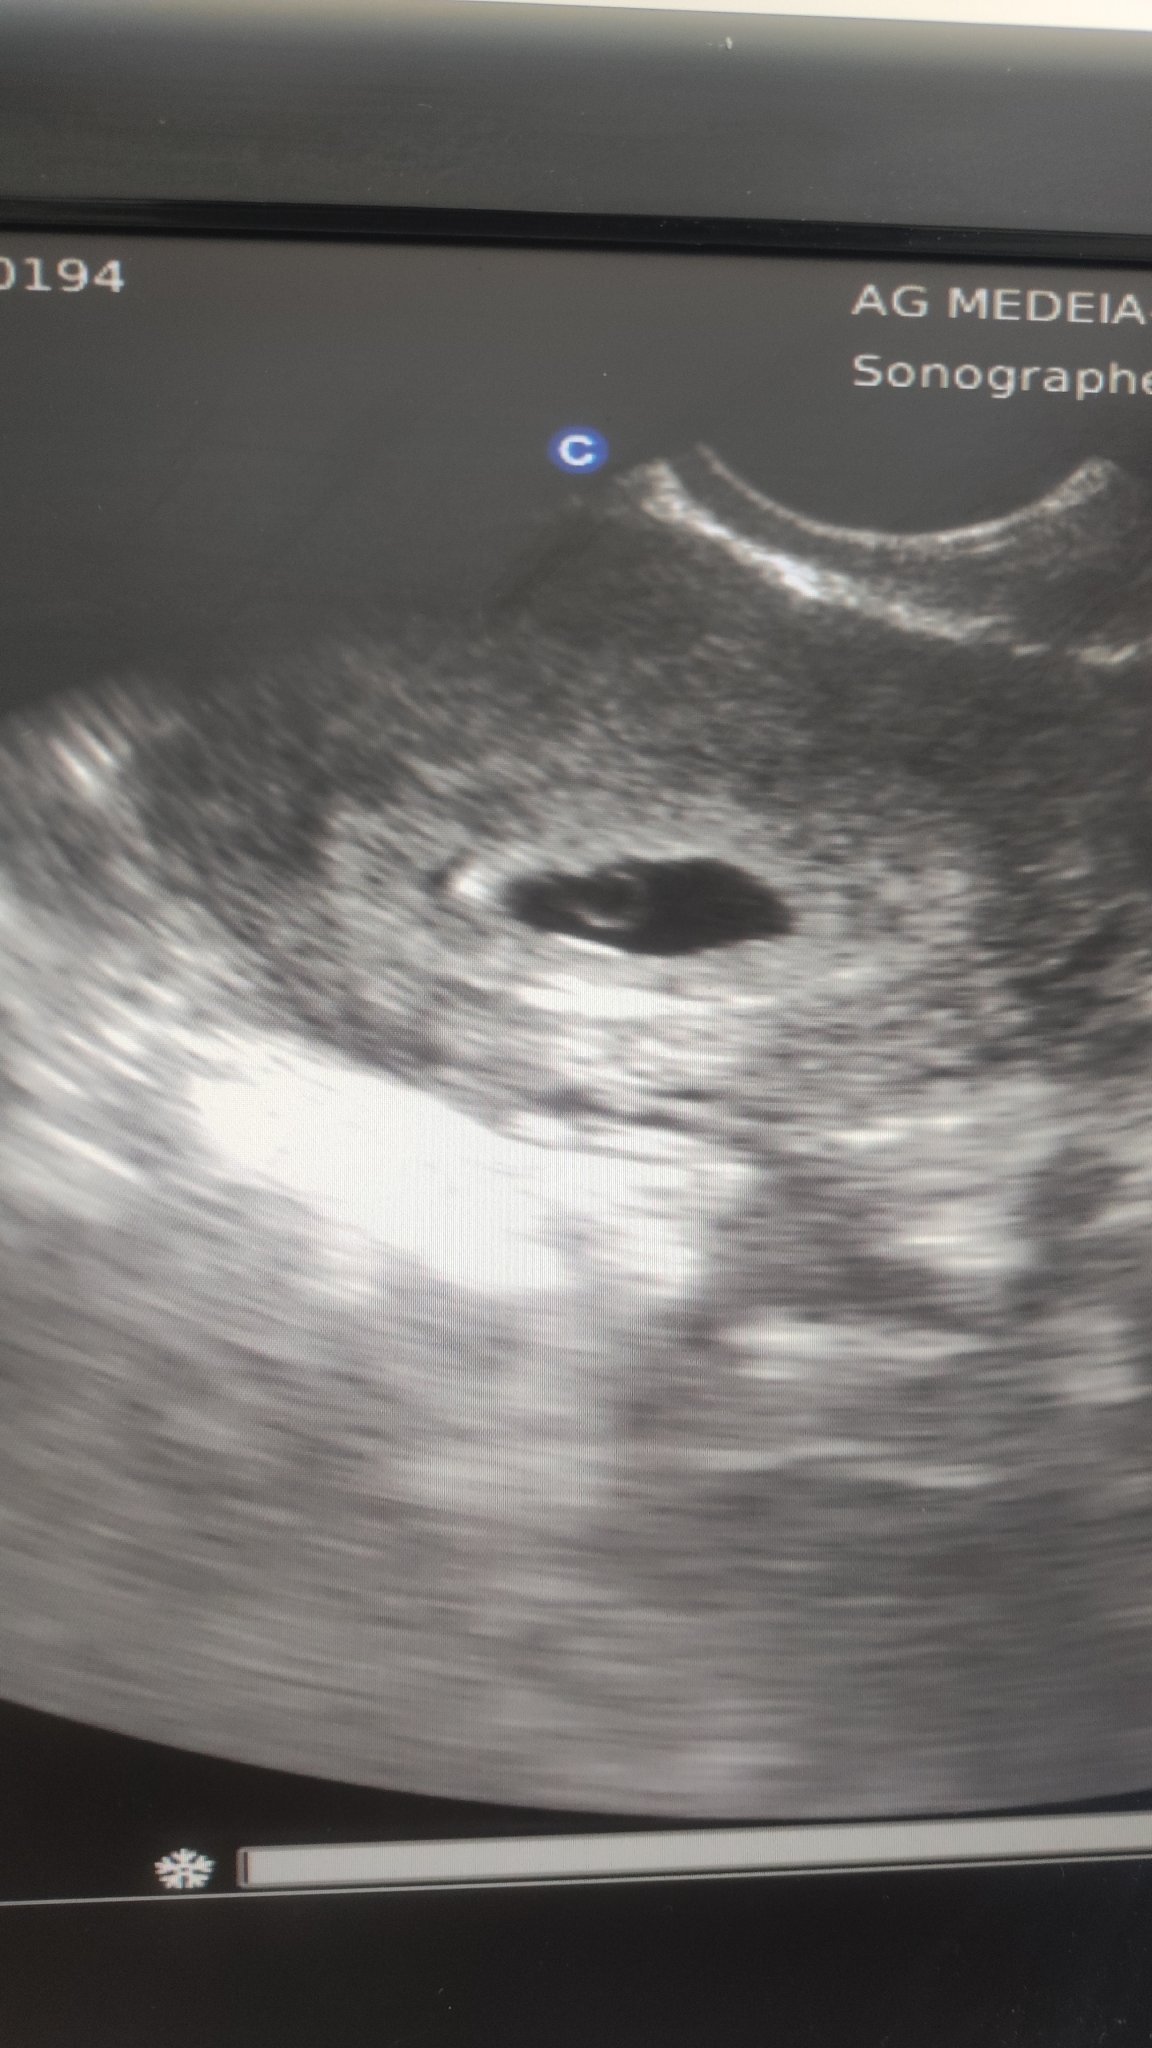

Здравейте , днес ми беше прегледа при АГ. Видя се само плоден сак и жълтъчно мехурче , ембрион не се видя. Според мои изчисления съм в 5 г.с. и 4 дни , а според ехографа сака отговаря на 6г.с. и 5 дни... Според вас нормално ли е това и защо не се вижда още ембрионче😞

Когато бластоцита попадне в матката започва да се излюпва (hatching), ако е по-дебела обвивката (zona pellucida) хетчингът може да продължи от 12-24 часа. След което започва имплантацията: ранна от 6 ден, при повечето жени 8-10 ден и късна 10-12 ден. Тя може да трае от 2-3 дни. Вие няма как да предвидите в какъв диапазон от време са се случили тези събития, ако ембриона се развива бързо - една седмица изпреварване отговаря на развитието, а не толкова на времето. А на въпроса, защо не се  вижда ембрионче само лекаря може да Ви отговори и зависи от чхг. Жълтъчен сак =1000-2000чхг. Ембрион чхг= 5000-6000. Всички тези данни се отнасят до трансвагинален ехограф, при коремен обикновено се вижда 1 седмица по-късно.

При някои се вижда на по-късен етап, може би трябва да се изчака 1 седмица и пак да се види на прегледа, дали има или не ембрионче. Дано има!

Илияна, за този срок на бременността сте видели достатъчно Blush има сакче и то където трябва. Когато отидете на следващия преглед, съветвам ви след десетина дни, ще се види ембриончето, а може би дори и сърдечна дейност (но не откачайте, ако още няма такава). Всяко нещо по реда си. Засега имате една съвсем нормално развиваща се бременност. Радвайте се Hug